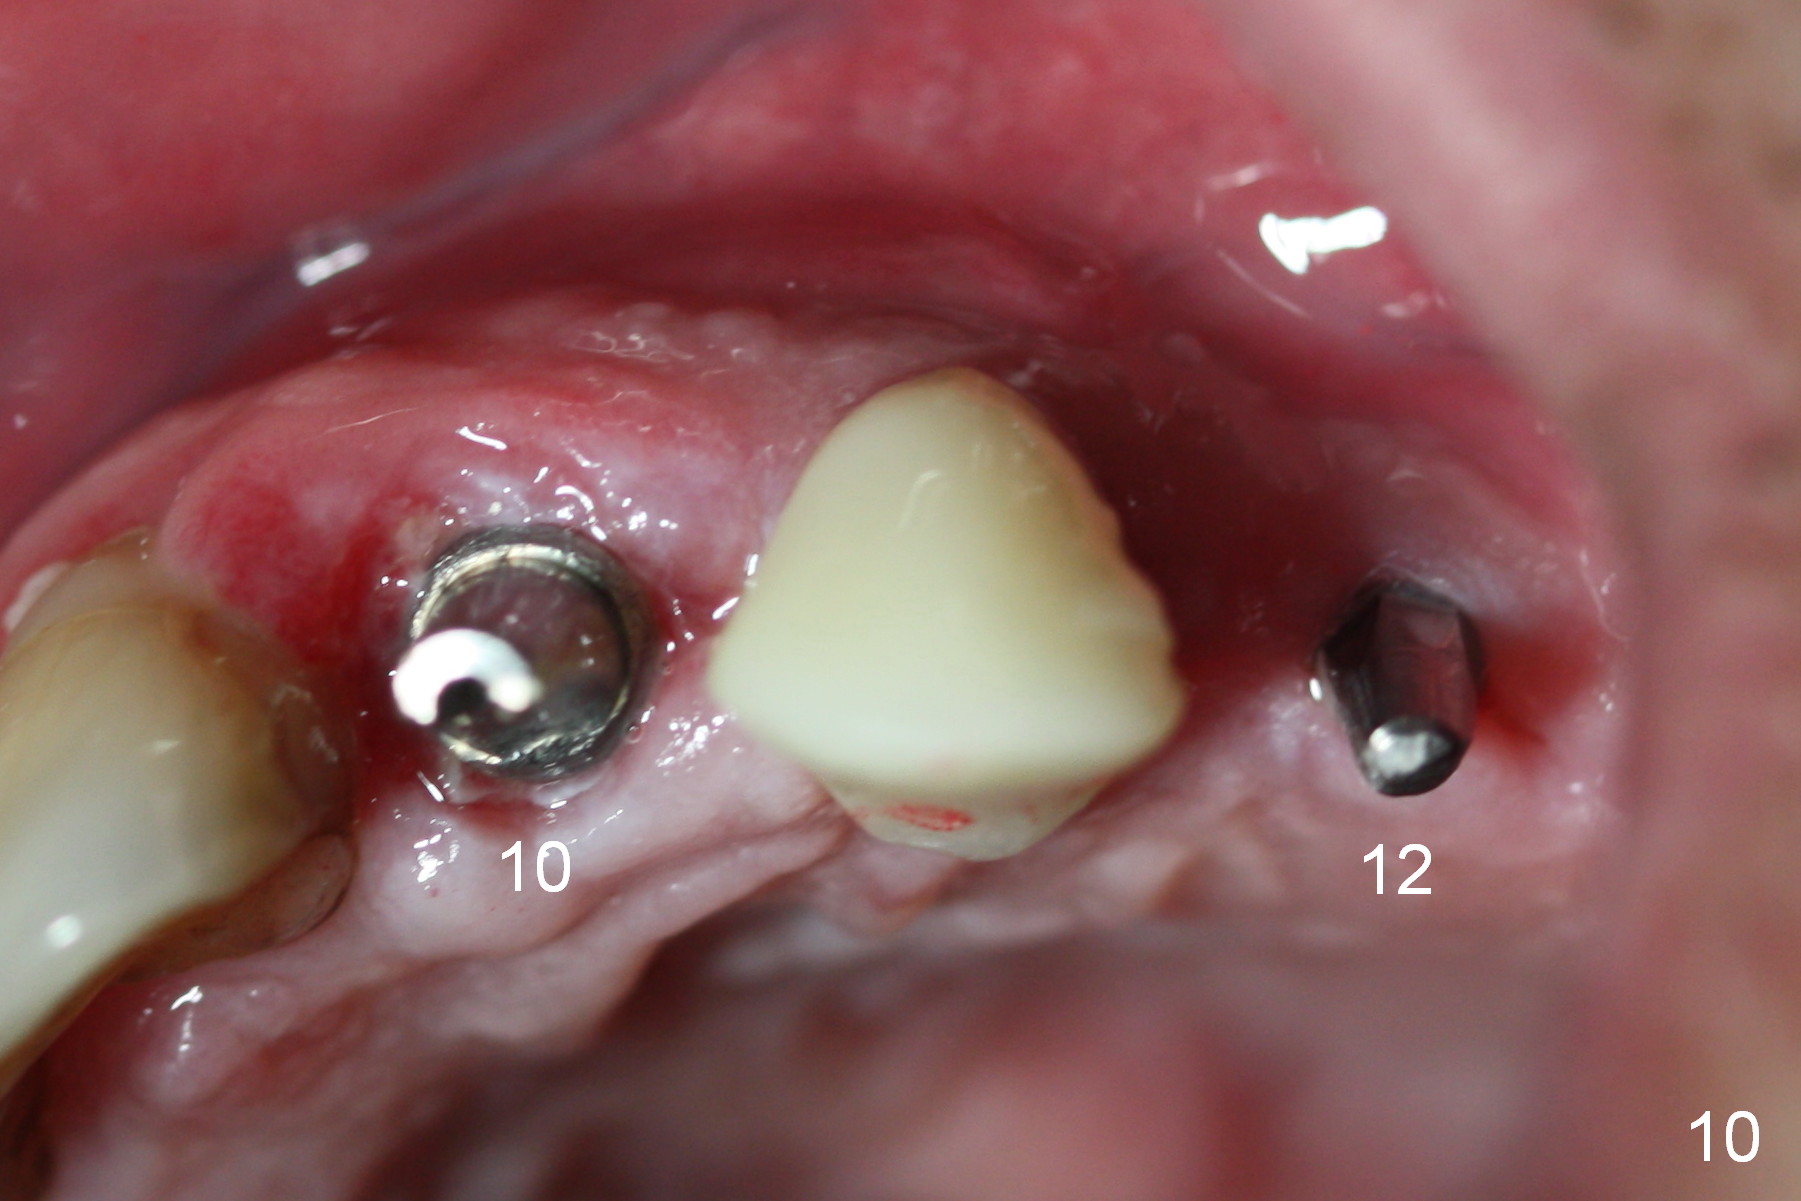

When the patient returns for implant placement (2nd visit after initial exam), he reveals that he is a dental phobic. He requests placement of 4 implants in the upper left quadrant, instead of 2. Narrow ridge is unexpected in the canine and premolar area (Fig.1). Limited bone height at #13 (Fig.3 arrowheads: sinus floor) is found when initial drills are in place (Fig.2,3). A 2-piece implant (4.5x17 mm tissue-level) is placed at #10 after extraction, while 1-piece implants are placed at 11 (3x17 mm (tissue-level, 15 °) and 12 and 13 (bone-level, 2.5x14, 12 mm, respectively; Fig.4,5). In fact the 1 piece implant at #13 is not completely placed (Fig.5). It is removed, the apical 3 threads are cut off (Fig.6 <, since a shorter implant was unavailable in the office) and the remaining implant is re-inserted. The insertion torques of the 4 implants are ~ 60, ~ 35, < 35 and 15 Ncm, respectively. After adjustment (Fig.7), immediate provisionals are fabricated at #10 and 11 (Fig.8, later splinted with composite), while perio dressing is applied around the implants at #12 and 13 and the provisionals at #10 and 11. There is no nasal hemorrhage postop. Although the perio dressing is loose 1 week postop (Fig.9), it is not removed. When the upper lip fissure (Fig.9 <) heals, provisionals at #12 and 13 are planned to be splinted to the other two ones. Two weeks postop, the upper lip fissure heals, the perio dressing dislodges and the implants at #12 and 13 are stable (Fig.10). After abutment height adjustment, a splinted provisional is fabricated over these 2.5 mm 1-piece implants (Fig.11).

The patient returns for final restoration 3.5 months postop; it appears that the implants have osteointegrated (Fig.12,13). After reprep, there is no gross buccal plate atrophy at #10 (Fig.14).